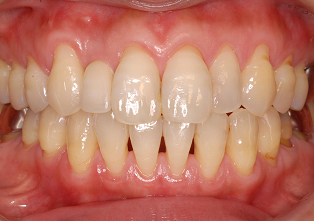

前歯部・審美領域の抜歯即時インプラント

右上の歯の前から2番目を抜歯し、即時にインプラントを施した前歯部・審美領域の治療

- 主訴

- 右上2の被せ物が取れた

- 治療内容

- 被せ物が脱離した右上2は歯根破折をしており、保存不可能と判断されたため抜歯と同時のインプラント埋入を計画。抜歯と同時にインプラント埋入。そのインプラントの生着を待って上部構造の装着を行なった

- 治療費用

- 435,000円(税別)

- 治療期間

- 3ヶ月